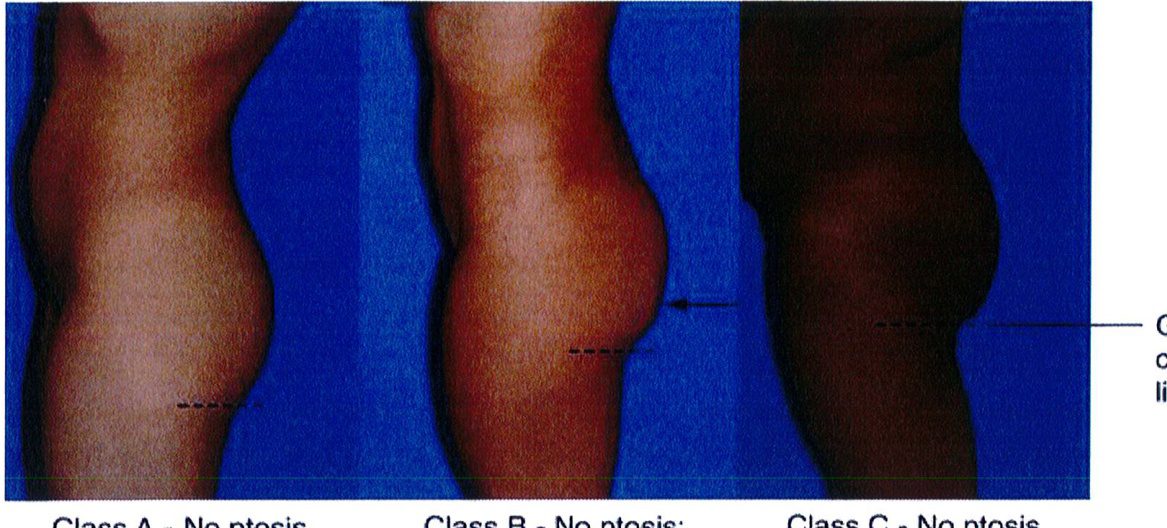

Bước cuối cùng khi đánh giá vùng mông là đánh giá tình trạng sa mông. Đế đánh giá, nên đứng ỏ phía bên để nhìn và phân loại sa mông (từ không sa đến có sa), cả 2 loại này đều được phân loại thành 3 phân lớp phía dưới chúng. Việc phân loại này quyết định xem nên thực hiện quy trình nào cho bệnh nhân.

Ở những bệnh nhân không có sa mông, toàn bộ vùng mông nằm trên nếp lắn mông và không có phần da thừa nằm dưới nếp lằn.

Tuy nhiên, dựa trên hình dạng vùng mông của đa số những bệnh nhân này, có thể chia thành 3 lớp: A, B và C (Hình 27).

Lớp A

Lớp C

ở những bệnh nhân thuộc lớp này, hầu hết phần mông nằm ở tập trung ở giữa, mô mỡ dưới da được phân bố đều ở phần mông trên và mông dưới. Ở mặt bên, không phát hiện tình trạng sa hoặc các vết lõm trên bề mặt, bờ mông có hình chữ C mềm mại. Lớp A này là hình dáng lý tưởng cho vùng mông, đặc biệt có tính thẩm mỹ cao khi nhìn từ phía bên. Những bệnh nhân thuộc lớp này chỉ cần thực hiện thủ thuật nâng mông đơn thuần.

Trong lớp C, da không bị xệ xuống dưới nếp lằn mông nhưng nếp này cũng không được nhìn thấy rõ ràng. Mỡ phân bố đều khắp mông khi nhìn từ phía bên. Phẫu thuật làm đầy mông nên được chỉ định cho những bệnh nhân này.

Lớp B

Class A – No ptosis

Class B – No ptosis: depression, lower part of central zone

Class C – No ptosis at crease

Hình. 27. Phân loại các bệnh nhân không có sa mông theo 3 lớp A, B, và C. Đường nét đứt biểu thị cho nếp lắn mông nhìn từ phía bên (đôi khi được gọi là crease).

Class A- No ptosis: Lớp A – Không sa Class B – No ptosis: depression, lower part of central zone: Lớp B – Không sa: Lõm ở phía dưới vùng trung tâm.

Class A- No ptosis: Lớp A – Không sa Class B – No ptosis: depression, lower part of central zone: Lớp B – Không sa: Lõm ở phía dưới vùng trung tâm. Class C – No ptosis at crease: Lớp C – Không sa xuống dưới nếp lằn mông. Gluteal crease line : Nếp lắn mông

Class C – No ptosis at crease: Lớp C – Không sa xuống dưới nếp lằn mông. Gluteal crease line : Nếp lắn mông